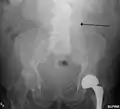

The faint outline of the calcified wall of an AAA as seen on plain X-ray

Abdominal aortic aneurysms (3.4 cm)